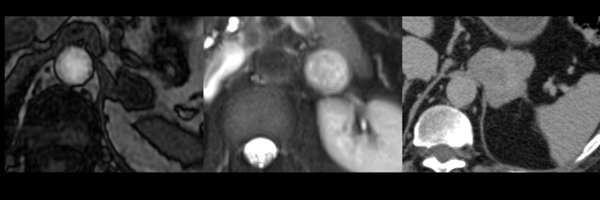

Glad to share the work of our DFP members on adrenal nodules with non-uniform signal loss on out of phase CS-MRI!! In patients with no history of malignancy, presence of heterogeneous microscopic fat indicates a high likelihood of benignancy. https://t.co/kssj9cpT6f

Please see the Editorial Comment by Julie H. Song discussing this article. BACKGROUND. Homogeneous microscopic fat within adrenal nodules on chemical-shift MRI (CS-MRI) is diagnostic of benign...

Assessment of heterogeneous adrenal nodules with washout CT. Very interesting @AJR_Radiology publication leaded by @MTCorwin in collaboration with @adrenaldfp members https://t.co/uCQ59iLtDQ

Beware of using washout CT In heterogeneous adrenal nodules. Great work @adrenaldfp @SocietyAbdRad. Thanks for your leadership @MTCorwin.